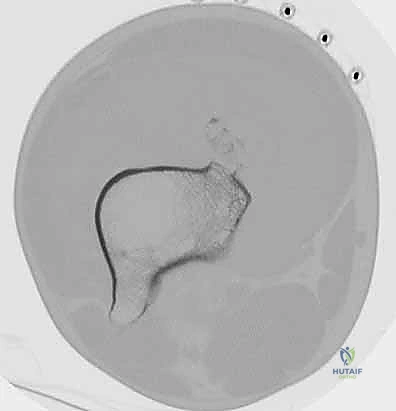

الخطوة الرابعة: تركيب الطرف الاصطناعي الضخم (Mega-Prosthesis)

يتم إدخال المكون الفخذي (الذي يعوض العظم المفقود) وتثبيته غالباً باستخدام الأسمنت العظمي الطبي (PMMA) أو بدونه حسب حالة العظم وعمر المريض. ثم يتم تركيب المكون الخاص بقصبة الساق (Tibia) وتوصيلهما معاً بمفصل مفصلي حديث (Hinged Knee) يسمح بالحركة ويمنع الخلع.

معرض صور: خطوات تركيب الطرف الاصطناعي بدقة

معرض الحالات الإشعاعية: توثيق النجاح الطبي مع د. محمد هطيف

الصور الإشعاعية قبل وبعد الجراحة هي الدليل القاطع على دقة ونجاح الإجراء الطبي. نستعرض هنا مجموعة من الصور التي توضح حجم الإنجاز الطبي في استبدال العظم المصاب بمفصل معدني متطور.